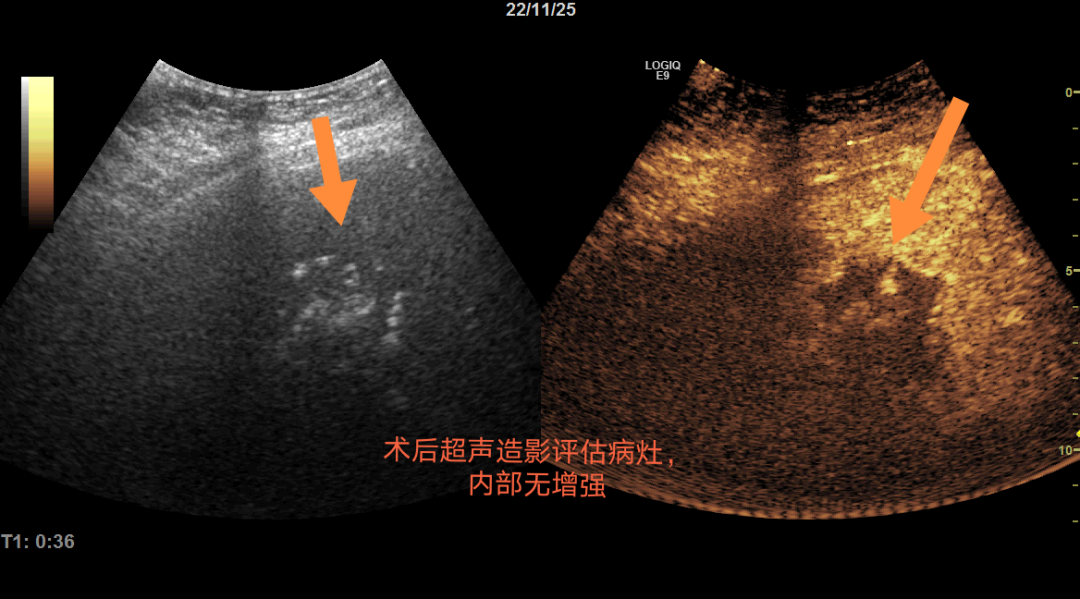

手术当天,从术前准备到手术结束,历时约50分钟。术后再次进行肝脏超声造影显示P女士肝脏转移灶达到了完全热消融,术后第二日患者即可下床活动,术后恢复2-3天即可出院。